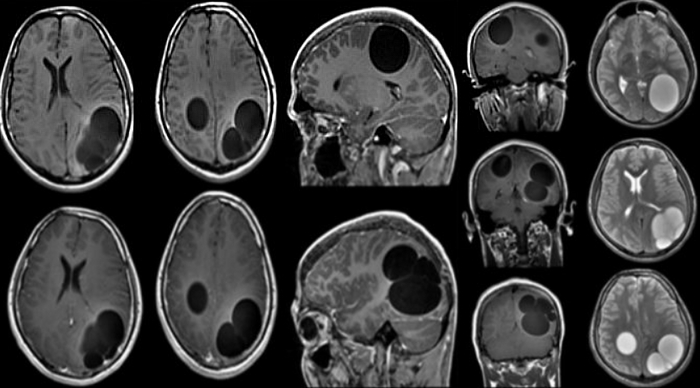

«Вот эти огромные черные пятна и есть те самые кисты, которые заняли всю правую долю моей печени, — показывая снимок КТ, говорит художница. — Самая большая киста была объемом целый литр. Внутри нее были личинки. Поэтому трогать этот пузырь нельзя было. Если хоть одна личинка попадет в кровоток, то зараза распространится повсюду».